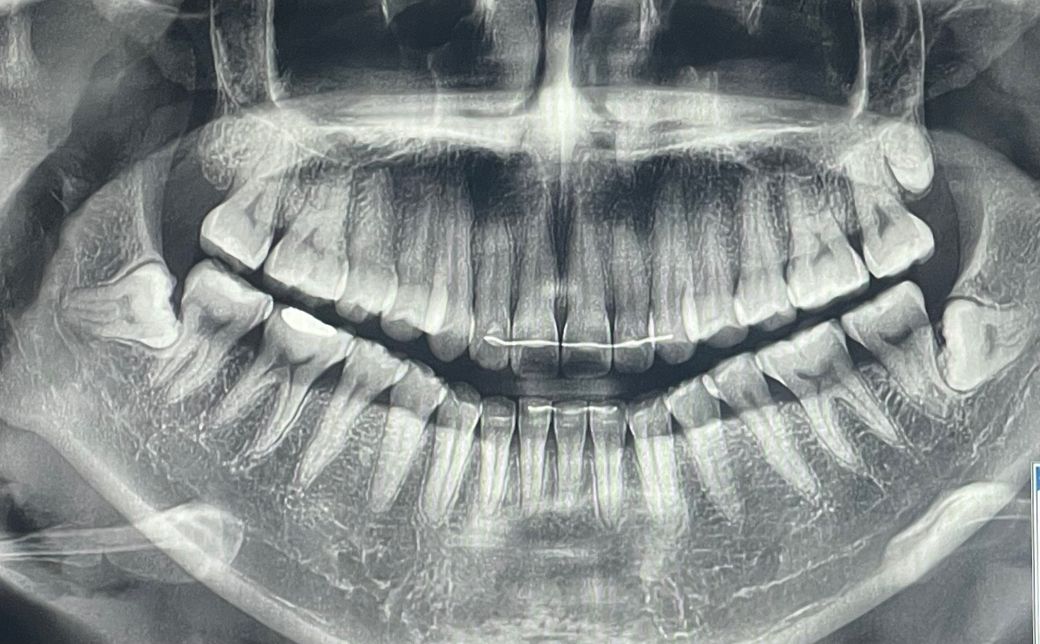

아래 양쪽에 완전 매복 사랑니가 있고 육안으론 보이지 않고 증상도 딱히 없습니다.

(위쪽에 있는건 사랑니가 나다가 만거겠죠? 저것도 혹시 빼야할까요..?)

지금까지 딱 한 번 왼쪽 사랑니쪽 잇몸이 살짝 부었던 적이 있는데 (사진 상 오른쪽) 하루쯤 지나니 다시 나아졌고 증상도 없어졌습니다.

저는 지금 만 33세인데요, 아래쪽 사랑니 두 개 꼭 발치를 해야하는 상황일까요...?

어금니 흡수?는 30대 이후엔 거의 잘 안일어난다고도 하던데 맞나요? 안그래도 구강구조가 좁고 자리가 많이 없는 편인데 30대 이후에도 치열에 계속 영향을 주는지도 궁금합니다.

1. 왼쪽 상악 사랑니는 아직 다 안자란건지? 그냥 두면 될지? 나중에라도 뽑아야할지?

2. 아래쪽 두 개 사랑니 발치가 꼭 필요할지

3.

30대 이상에선 뼈 흡수? 같은

경우는 많이 없다고 하던데 뼈 흡수?나 치열, 다른 치아에 영향을 줄 가능성이 높은지

4. 실제로 구강구조가 많이 좁아서 육안으로 봤을 때 어금니 뒤쪽 자리는 거의 자리가 없는데 엑스레이상으론 틈이 보이시는지?? 앞쪽 어금니 충치나 사랑니부근 잇몸 염증 가능성이 있을지 (한번 잠깐 붓고 아팠던 적은 있으나 앞으로 자주 아파질 가능성이 클지)

5. 30대 중반 사랑니 발치, 제 케이스는 많이 난이도가 높을지

1. 다 자란 거고, 모양이 저렇게 생긴겁니다. 사랑니는 형태가 다양합니다. 상악은 그냥 둬도 될 것 같습니다

2. 하악은 예방적으로 빼주면 좋을 것 같긴 합니다.

3. 하악 사랑니가 문제가 될 수 있는 경우는 옆 어금니에 영향을 주어 치근흡수, 치근우식(충치)를 만드는 겁니다.

4. 잇몸에 가려져 있으니 당연히 안보일건데 사랑니로 인해 잇몸 염증도 유발될 수 있습니다.

5. 난이도 높습니다. 신경관과 거리도 가까워 주의해야 합니다.